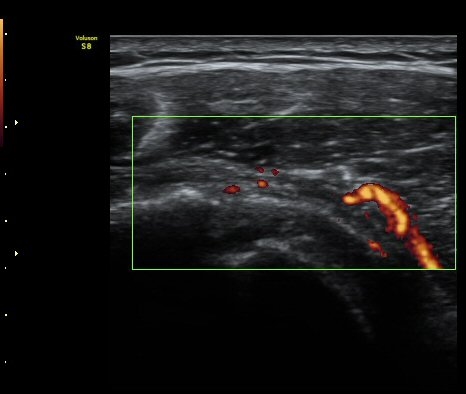

ȸÀü±Ù°³°£°Ý(rotator cuff interval) Ⱦ´Ü¸é°Ë»ç¿¡¼­ Á¡¾×³¶¸Å ¼ö¾× Àú·ù°¡ °üÂûµÈ´Ù(±×¸² 1).

ÆÄ¿öµµÇ÷¯°Ë»ç¿¡¼­ ±Ø»ó°Ç°ú Á¡¾×³¶ÁÖÀ§¿¡¼­ ¼ö¾×Àú·ù°¡ °üÂûµÈ´Ù(±×¸² 6, 7).